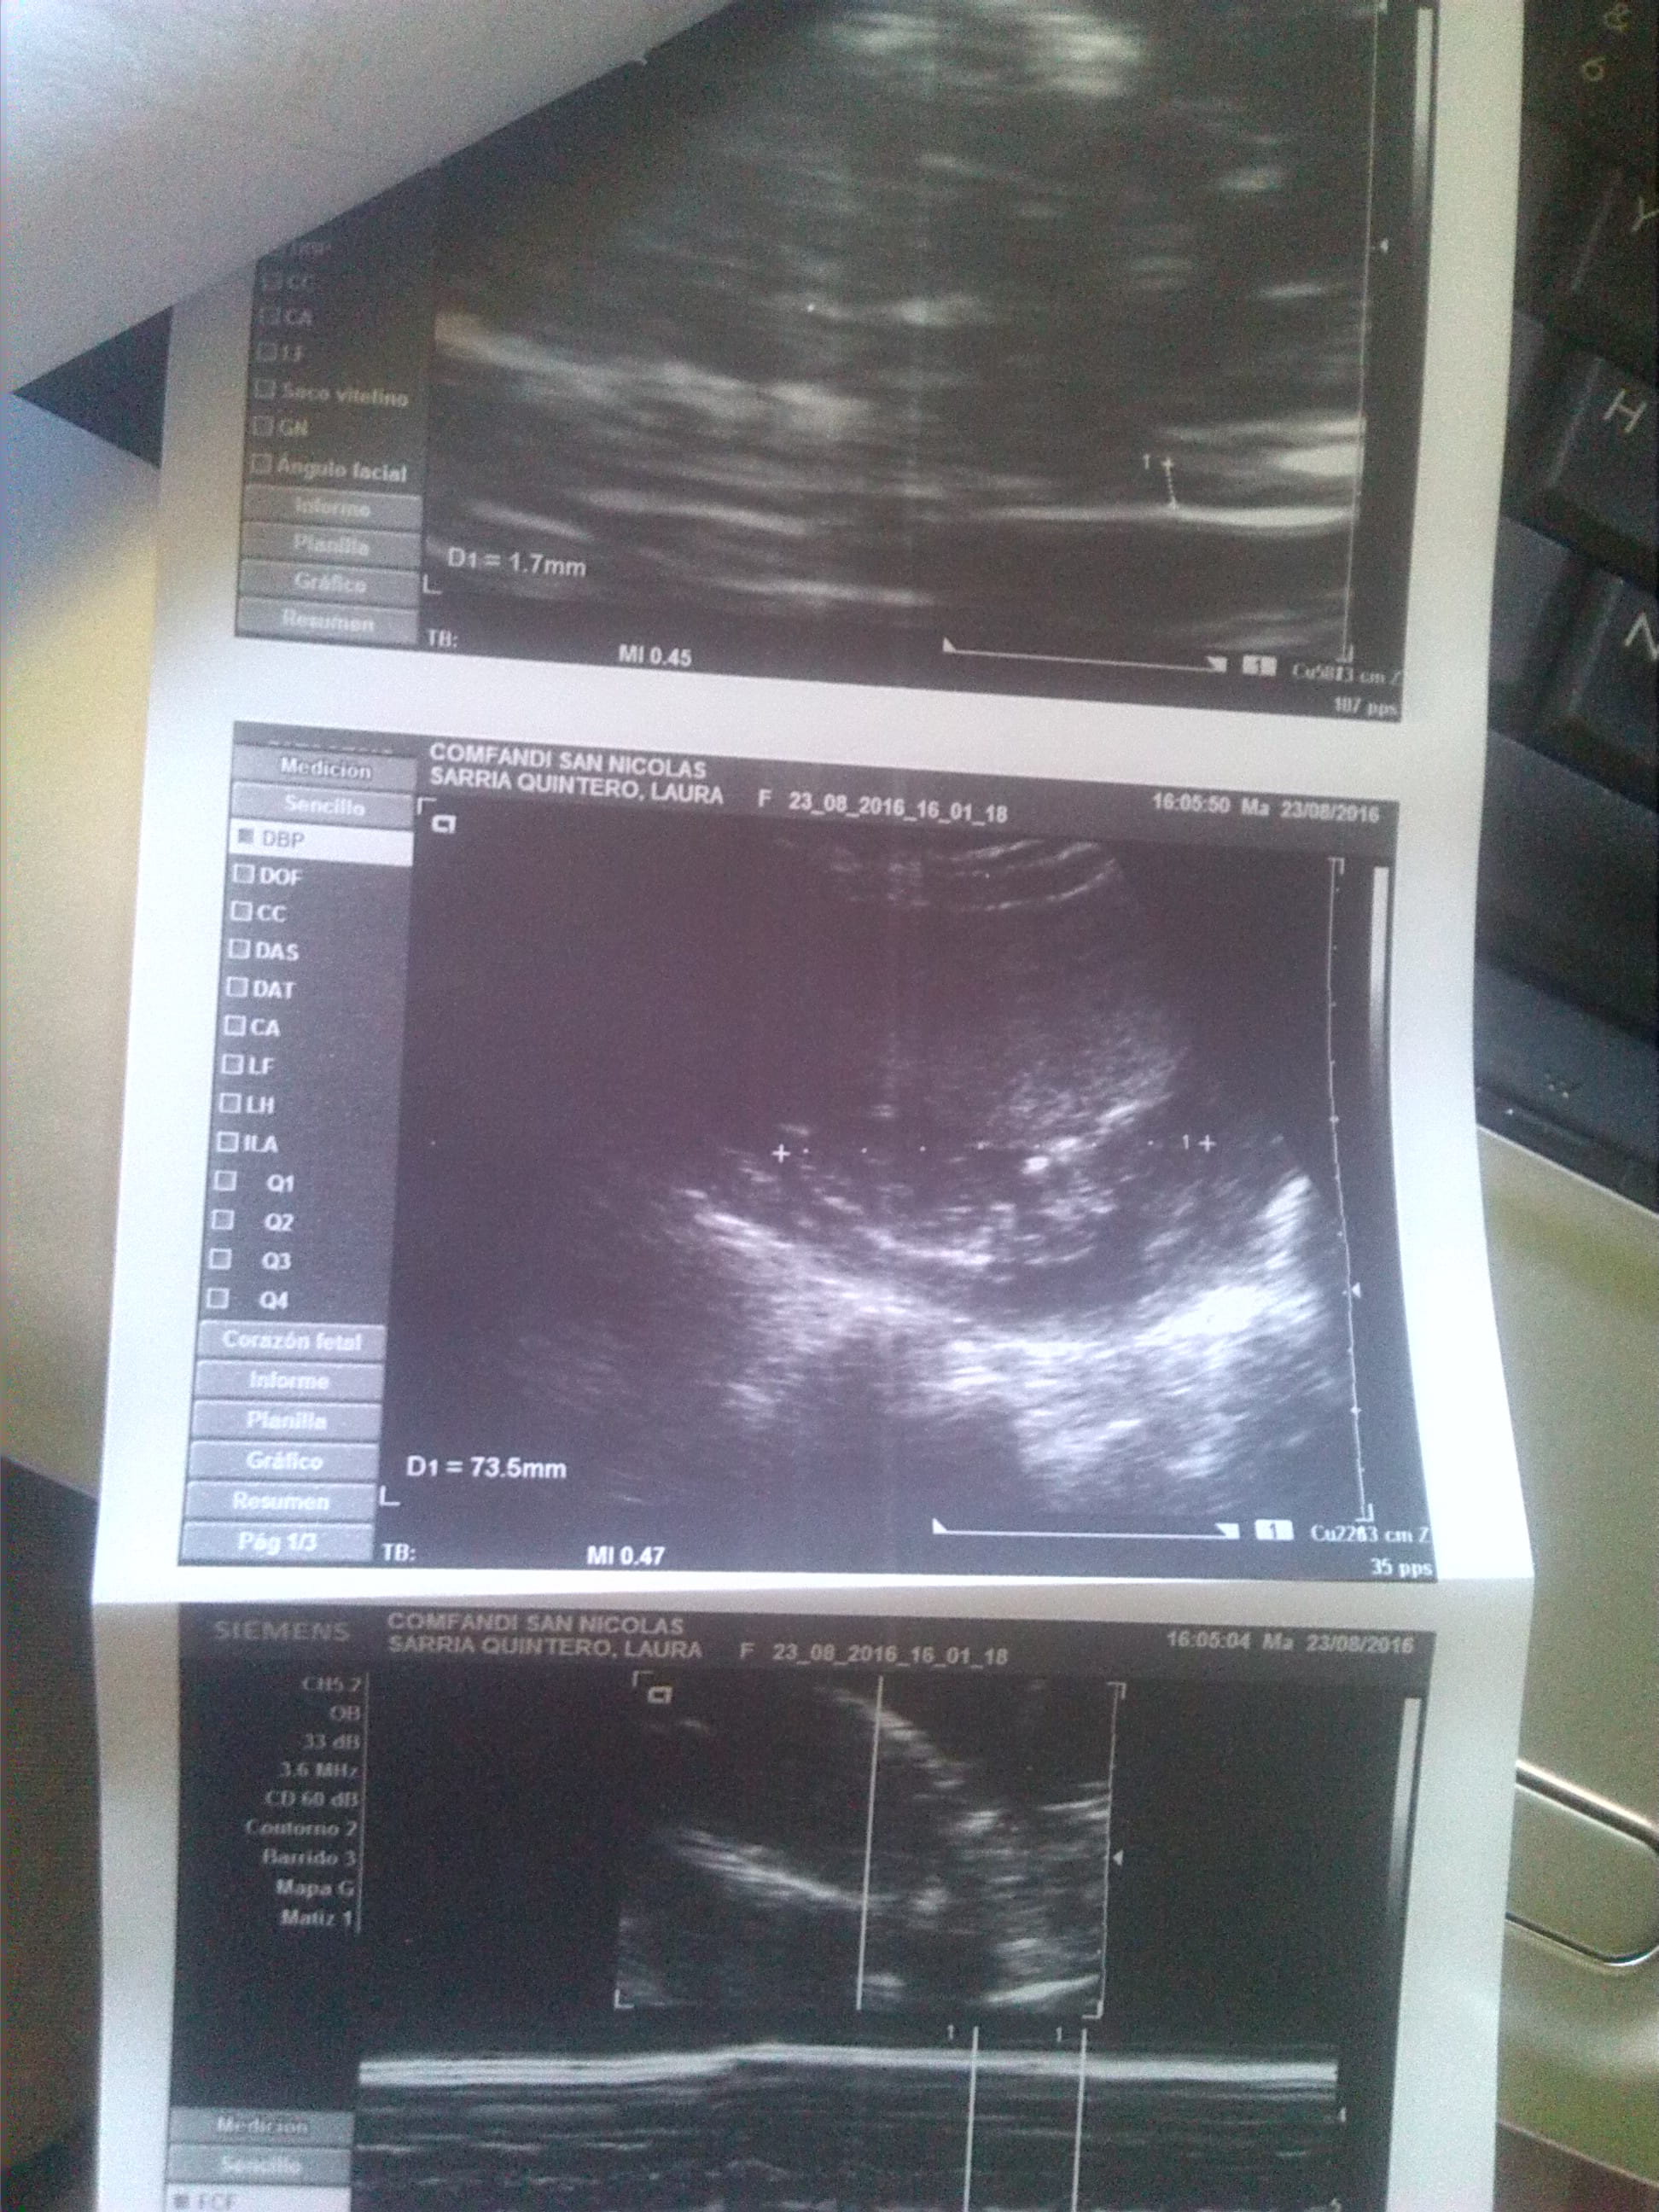

Hola buenos dias lo que les queria comentar el dia de hoy es que me hicieron la ecografia el dia e ayer a lo que corresponde a 13 + 5 semanas para latidos del corazon de 150 xm mi ginecologo